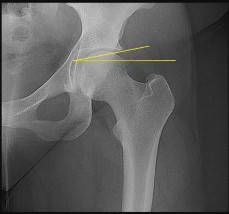

A 13-year-old overweight male presents with an acute exacerbation of chronic right groin and knee pain. He walks with an externally rotated gait. Radiographs confirm a severe Slipped Capital Femoral Epiphysis (SCFE).

Pathophysiologically, the slippage in SCFE occurs primarily through which specific histological zone of the proximal femoral physis?

Explanation

Slipped Capital Femoral Epiphysis (SCFE) typically occurs due to mechanical shear forces across a weakened physis during the adolescent growth spurt. Histologically and biomechanically, the weakest layer of the growth plate is the zone of hypertrophy. The slippage classically occurs through this layer because the chondrocytes are enlarged, and the extracellular matrix is sparse compared to the reserve or proliferative zones, making it highly susceptible to shear stress.